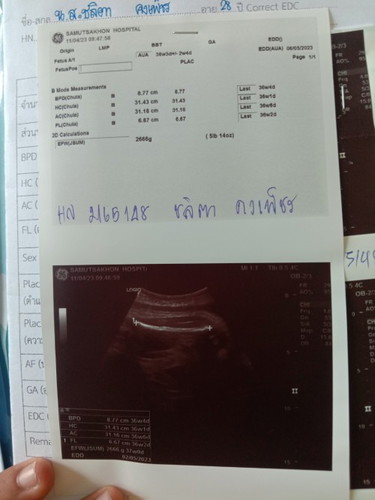

พอจะดูกันออกไหมค่ะทุกคน

มันมั้ยมีขึ้นตรงอัลตราซาวด์เหรอค่ะ

แม่ท้อง